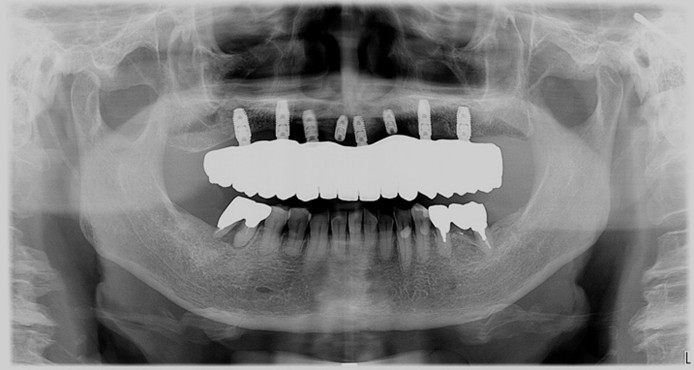

症例1

| 術前 | 術後 |

| ご来院時の主訴 | 入れ歯を入れたが落ちてくる。 インプラントの話を聞いたので入れ歯じゃなくてインプラントをしたい。 |

| 年代・性別 | 70代 女性 |

| 治療部位 | 上顎7〜7 |

| 治療費用 | 2,420,000円 |

| 手術回数 | 2回 |

| 治療期間 | 25か月 |

| 手術時間 | 90分×2回 |

| 治療回数 | 28回 |